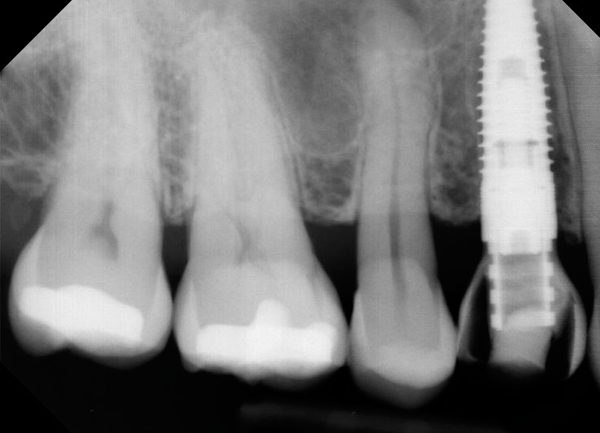

Fig 4. Flared abutments (healing or definitive) that encroach on the biologic width of the peri-implant bone will also result in apical remodeling. This is likely to compromise the critical crest of bone on the adjacent teeth that is largely responsible for supporting the papilla.

Figure 4